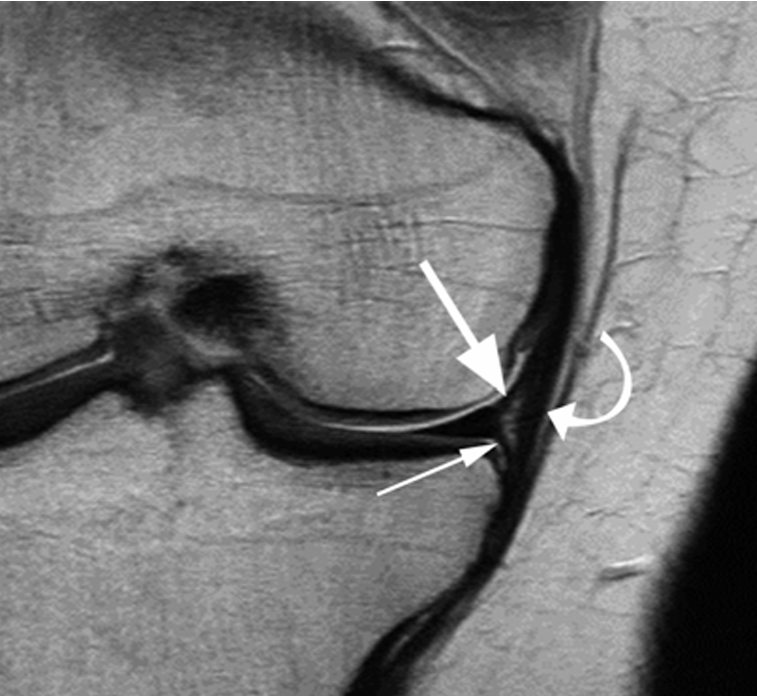

Mas ligamentos meniscales. Los oblicuos laterales. Fig. 5.7 La imagen FSE axial (PD) muestra el ligamento oblicuo lateral (flechas) que conecta el asta posterior del menisco medial (flecha curvada) con el cuerno anterior del menisco lateral